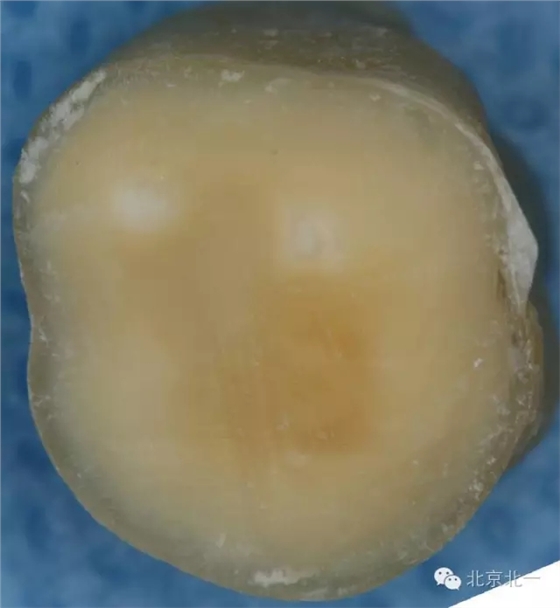

這只是因為學(xué)生們對于牙體組織的顏色沒有很好的理解,髓頂?shù)纳珴膳c其下方髓底的顏色有著顯著的不同(下圖為同一顆牙不同層面的片切圖A為髓頂與穿髓孔B為下方的髓底與根管口)。